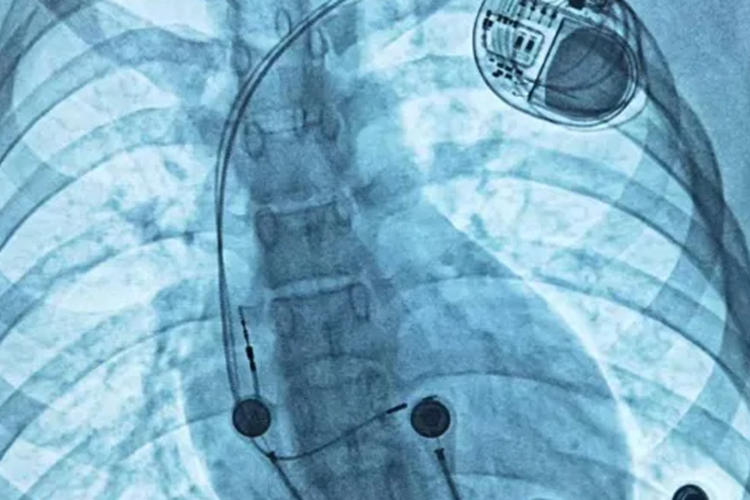

心脏起搏器的寿命受起搏器类型、起搏模式、患者心脏状况、电池技术质量以及日常使用维护等因素影响,在5-15年不等,应密切配合医生进行随访和管理,以确保起搏器的正常运行和延长其使用寿命,保障心脏健康。

1、起搏器的类型:单腔起搏器,只有一根电极导线连接心房或心室,其电池寿命一般在8-12年,适用于特定的心律失常患者。患者应定期进行起搏器程控检查,了解起搏器的工作参数和电池状态。日常生活中避免剧烈运动和撞击起搏器植入部位。

4、电池技术和质量:先进的电池技术和高质量的电池能够延长起搏器的使用寿命。目前新型起搏器的电池寿命可达10-15年。但随着使用时间的推移,电池性能会逐渐下降。患者在植入起搏器前,可与医生充分沟通,了解不同起搏器的电池特点。术后要避免接触强磁场和高电压环境。